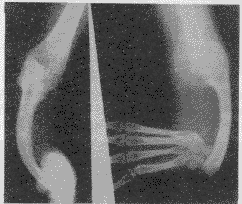

X线检查:右桡骨缺如,并第一掌、指骨、舟骨、大多角骨缺如。同侧尺骨短小弯曲,凹面不光滑向尺侧,尺侧骨皮质增宽,近段呈轻度波浪状改变。外周软组织影变薄,肌间隙增宽。尺骨与手垂直畸形,肘关节未见脱位征象。

附图 右桡骨缺如,第一掌、指骨、舟骨、大多角骨缺如。尺骨短小弯曲,尺骨与手呈垂直畸形之“拐状手”改变。外周软组织影变薄, http://www.100md.com